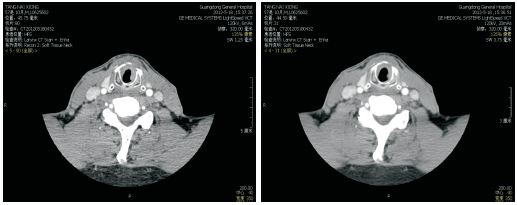

2014-03-26喉增强MRI:喉部术后改变, 喉腔内见巨大软组织肿块影, 大小约41 mm× 29 mm, 信号均匀, 边界不清, 增强后病灶明显均匀性强化, 喉腔变窄、消失, 病灶向上累及会厌皱襞, 下缘达甲状腺水平, 见图6和图7, 无病生存期14个月。

诊断:喉鳞状细胞癌术后造瘘口复发rT4aN0M0 Ⅳ A期。